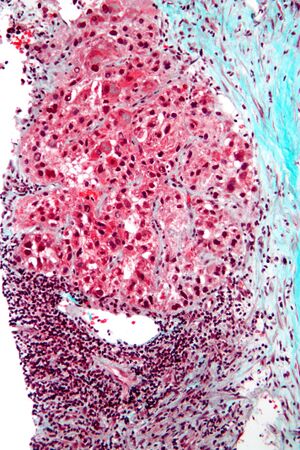

Pathology

Macroscopically, liver cancer appears as a nodular or infiltrative tumor. The nodular type may be solitary (large mass) or multiple (when developed as a complication of cirrhosis). Tumor nodules are round to oval, gray or green (if the tumor produces bile), well circumscribed but not encapsulated. The diffuse type is poorly circumscribed and infiltrates the portal veins, or the hepatic veins (rarely).[16]

Microscopically, the four architectural and cytological types (patterns) of hepatocellular carcinoma are: fibrolamellar, pseudoglandular (adenoid), pleomorphic (giant cell), and clear cell. In well-differentiated forms, tumor cells resemble hepatocytes, form trabeculae, cords, and nests, and may contain bile pigment in the cytoplasm. In poorly differentiated forms, malignant epithelial cells are discohesive, pleomorphic, anaplastic, and giant. The tumor has a scant stroma and central necrosis because of the poor vascularization.[39] A fifth form – lymphoepithelioma like hepatocellular carcinoma – has also been described.[40][41]

-

Well-differentiated HCC

Moderately differentiated HCC.

Poorly differentiated HCC